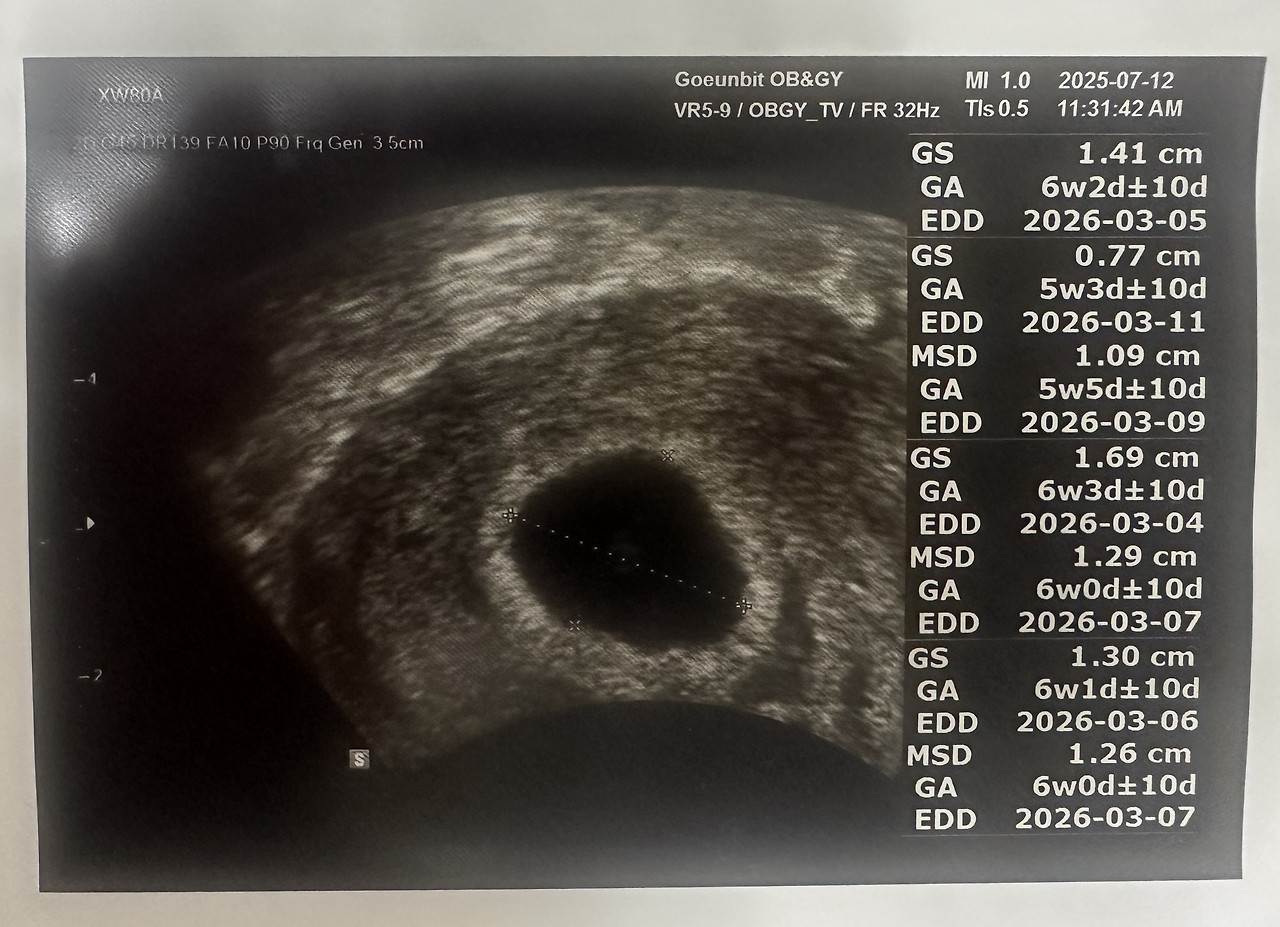

“7주 차네요. 아직 작지만 아기집은 잘 보입니다.”

7주2일 (1).jpg 7주 2일 차

7주2일 (5).jpg 7주 2일 차